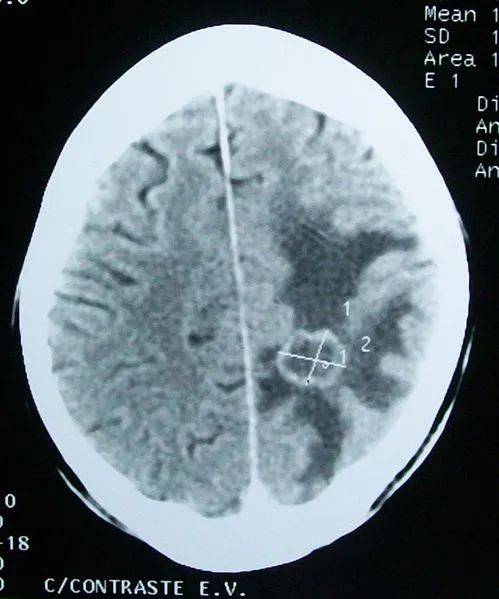

癌细胞扩散的ct图片

癌细胞扩散的ct图片,癌细胞图片扩散